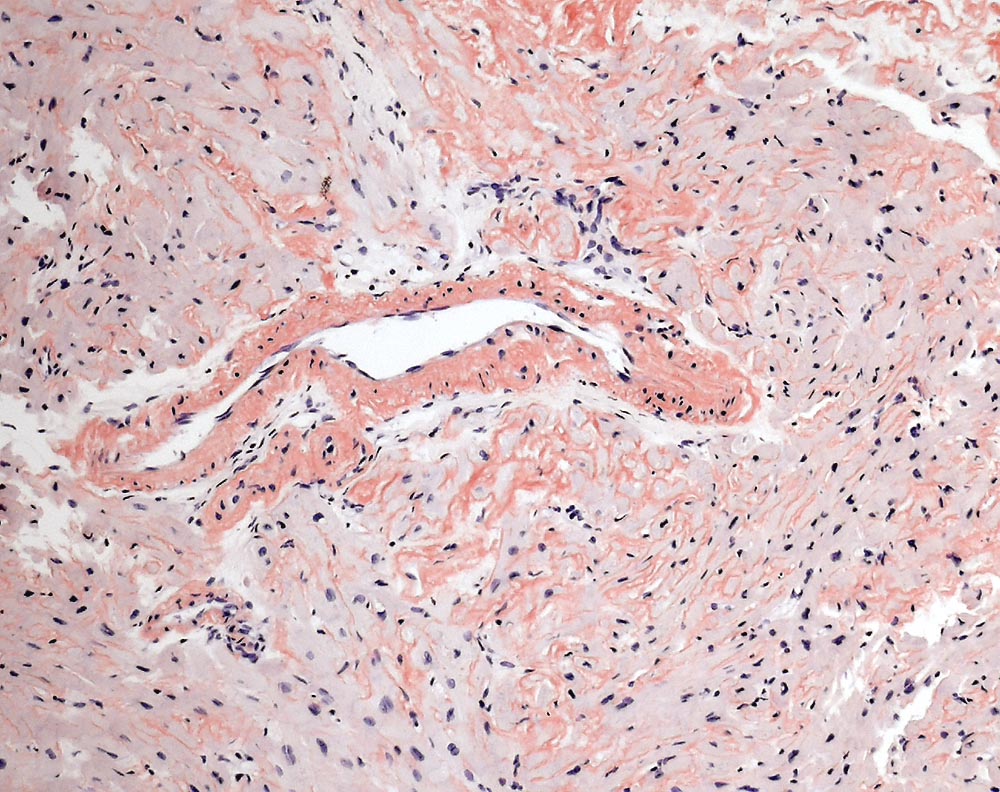

Interstitielle und vaskuläre kongorote Amyloidablagerungen.

Interstitielle Knochenmarksinfiltration durch ein lambdaklonale Plasmazellneoplasie, Infiltrationsvolumen 15-20% der kernhaltigen Knochenmarkszellen. AL-Amyloidose der Knochenmarksgefässe.

Zunehmende Dyspnoe über die vergangenen 2 Jahre. Multiples Myelom mit freien Leichtketten vom Typ Lambda. TTE: Ausgeprägt konzentrisch hypertropher linker Ventrikel mit normaler systolischer Globalfunktion ohne regionale Motilitätsstörungen (EF 60%). Diastolische Dysfunktion Grad 3 bis 4 (restriktive Füllungsmuster).